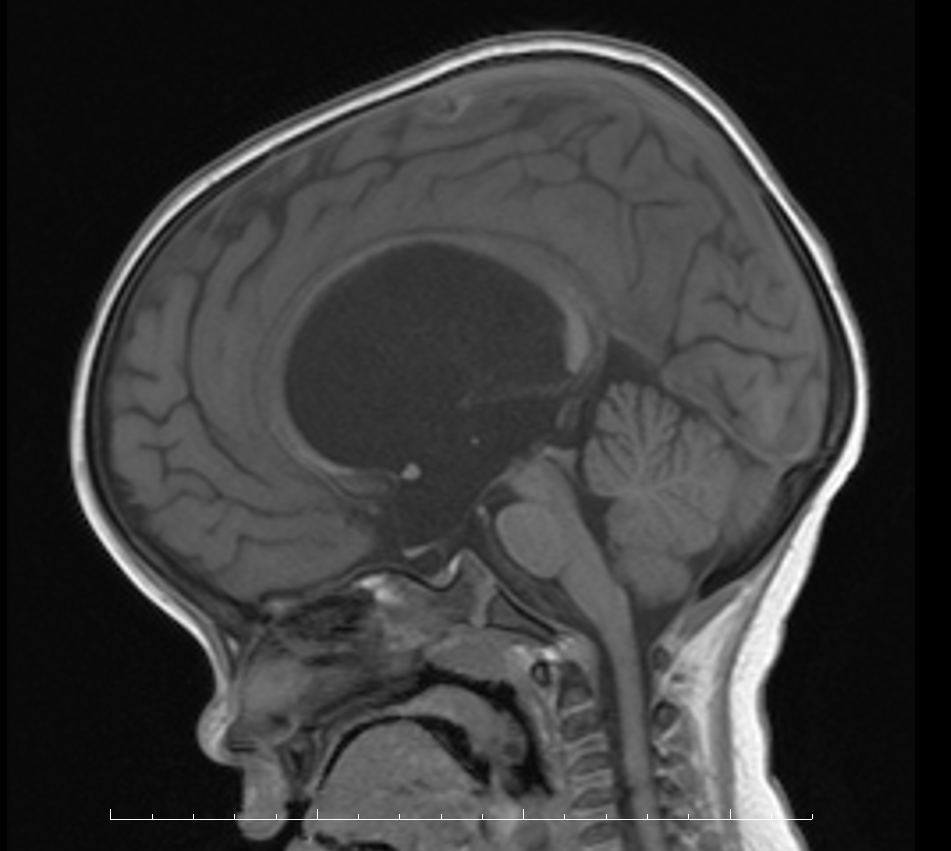

小瑞是一个菲律宾出生的中国国籍混血小男孩,在菲律宾务工的中国帅小伙浪漫邂逅了菲律宾美女,生下一个漂亮的混血宝宝小瑞。父母看到活泼可爱的小瑞一天天长大感觉非常幸福,然而好景不长,父母发现2岁的小瑞语言、运动发育均落后同龄儿童,本来会叫爸爸妈妈的小瑞慢慢不会说话也不会走路了,头围比同龄小朋友大了许多,达到55.5cm,有一个成人的头那么大。万分焦急的父母带小瑞辗转于菲律宾各家医院检查后明确诊断了脑积水,但都没有给出进一步治疗。看着小瑞一天天长大,但病情却逐渐加重,和同龄小朋友智力上的差距也越来越明显。焦急的父母等到国内疫情缓解后便马不停蹄的带着小瑞回到祖国,通过当地医生联系湖南省儿童医院神经外科。虽然正值暑期就医高峰,科室考虑到小瑞的特殊情况,开辟绿色通道第一时间给小瑞办理了住院手续。入院后行头部MRI提示中脑导水管变窄、幕上重度脑积水并间质性脑水肿。

图一 术前头部MRI检查

给小瑞完成术前检查及准备后,于7月5日上午,在麻醉手术科的全程保驾护航下,刘景平手术团队按计划成功为小瑞实施了脑室镜探查三脑室底造瘘手术,术中脑室镜探查右侧脑室,见侧脑室扩张明显,透明隔部分缺如,右侧室间孔扩大,经右侧室间孔进入三脑室的脑室镜成功进行三脑室底造瘘,建立了新的脑脊液循环,治愈了小瑞的脑积水。整个手术操作过程不到1个小时,手术过程顺利,术后小瑞病情平稳。术后复查头部CT提示小瑞脑积水较术前明显好转。